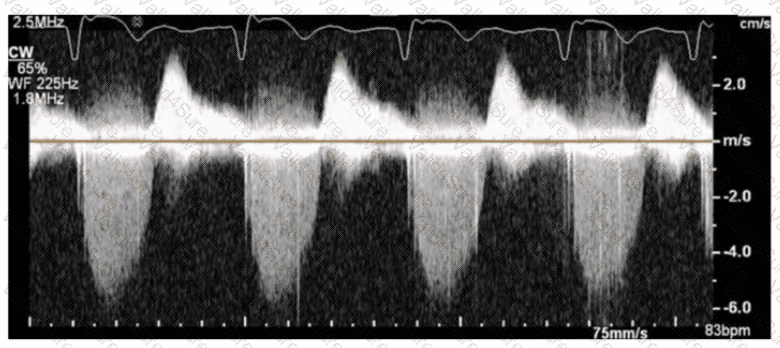

The sonographer obtains this Doppler signal while using the non-imaging transducer in the apical position. What is the best way to differentiate between mitral regurgitation and aortic stenosis signals in the waveform shown in this image?